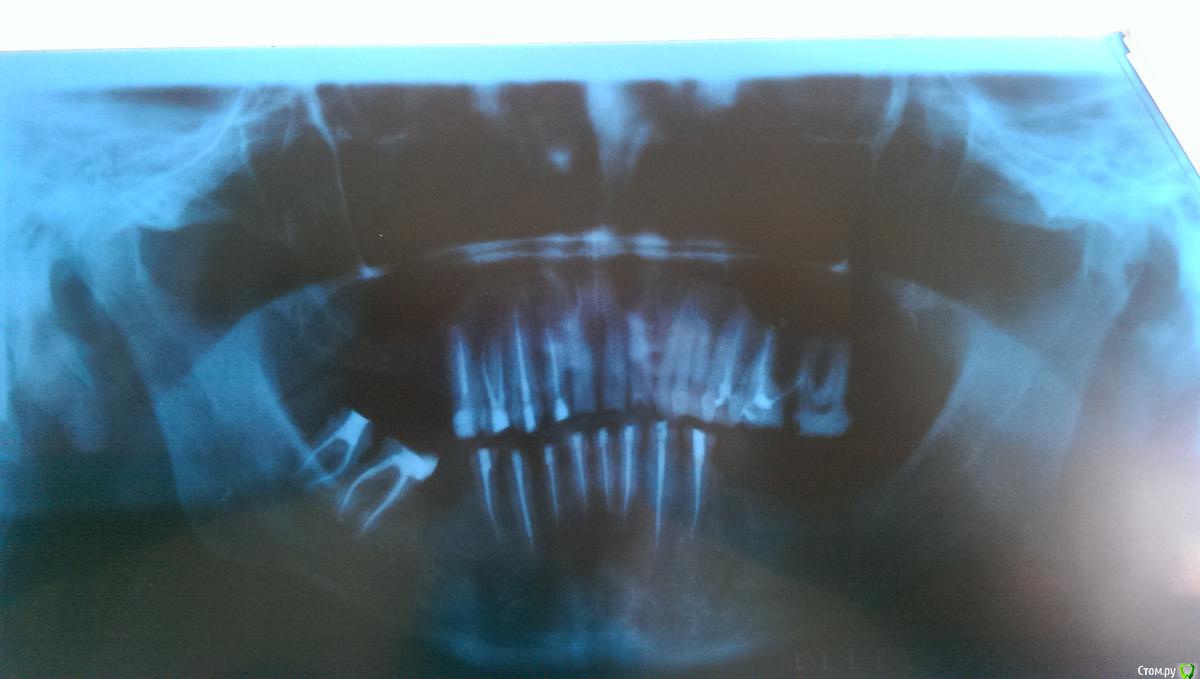

Ром@н Опубликовано 12 мая, 2015 Автор Поделиться Опубликовано 12 мая, 2015 Вот пациент вернулся и даже сделам ОПТГ Ссылка на комментарий

Ром@н Опубликовано 12 мая, 2015 Автор Поделиться Опубликовано 12 мая, 2015 ОПТГ КАЧЕСТВО С ТЕЛЕФОНП Ссылка на комментарий

Dr.Berlinale Опубликовано 22 мая, 2015 Поделиться Опубликовано 22 мая, 2015 Судя по снимкам, все должно держаться. Ссылка на комментарий